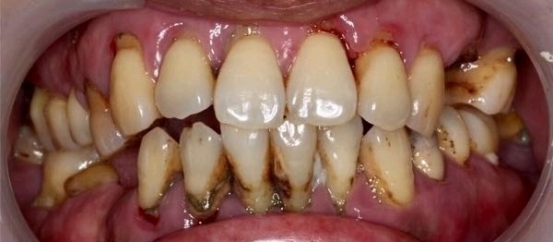

牙周炎

牙周炎是牙齿周围组织的炎症,它会导致牙齿周围组织红肿、易出血,长期的炎症反应还会破坏和吸收牙槽骨,是成年人牙齿松动甚至脱落的首要原因。

牙周炎就如同树根周围土壤水土流失,以至于树木无法固定在地上一样。牙周炎的主要病因是细菌以及牙结石,良好的口腔卫生习惯、定期洁牙(洗牙)可有效预防牙周炎。

重度牙周炎的示意图

牙周病导致牙龈萎缩、牙根暴露,甚至牙齿松动